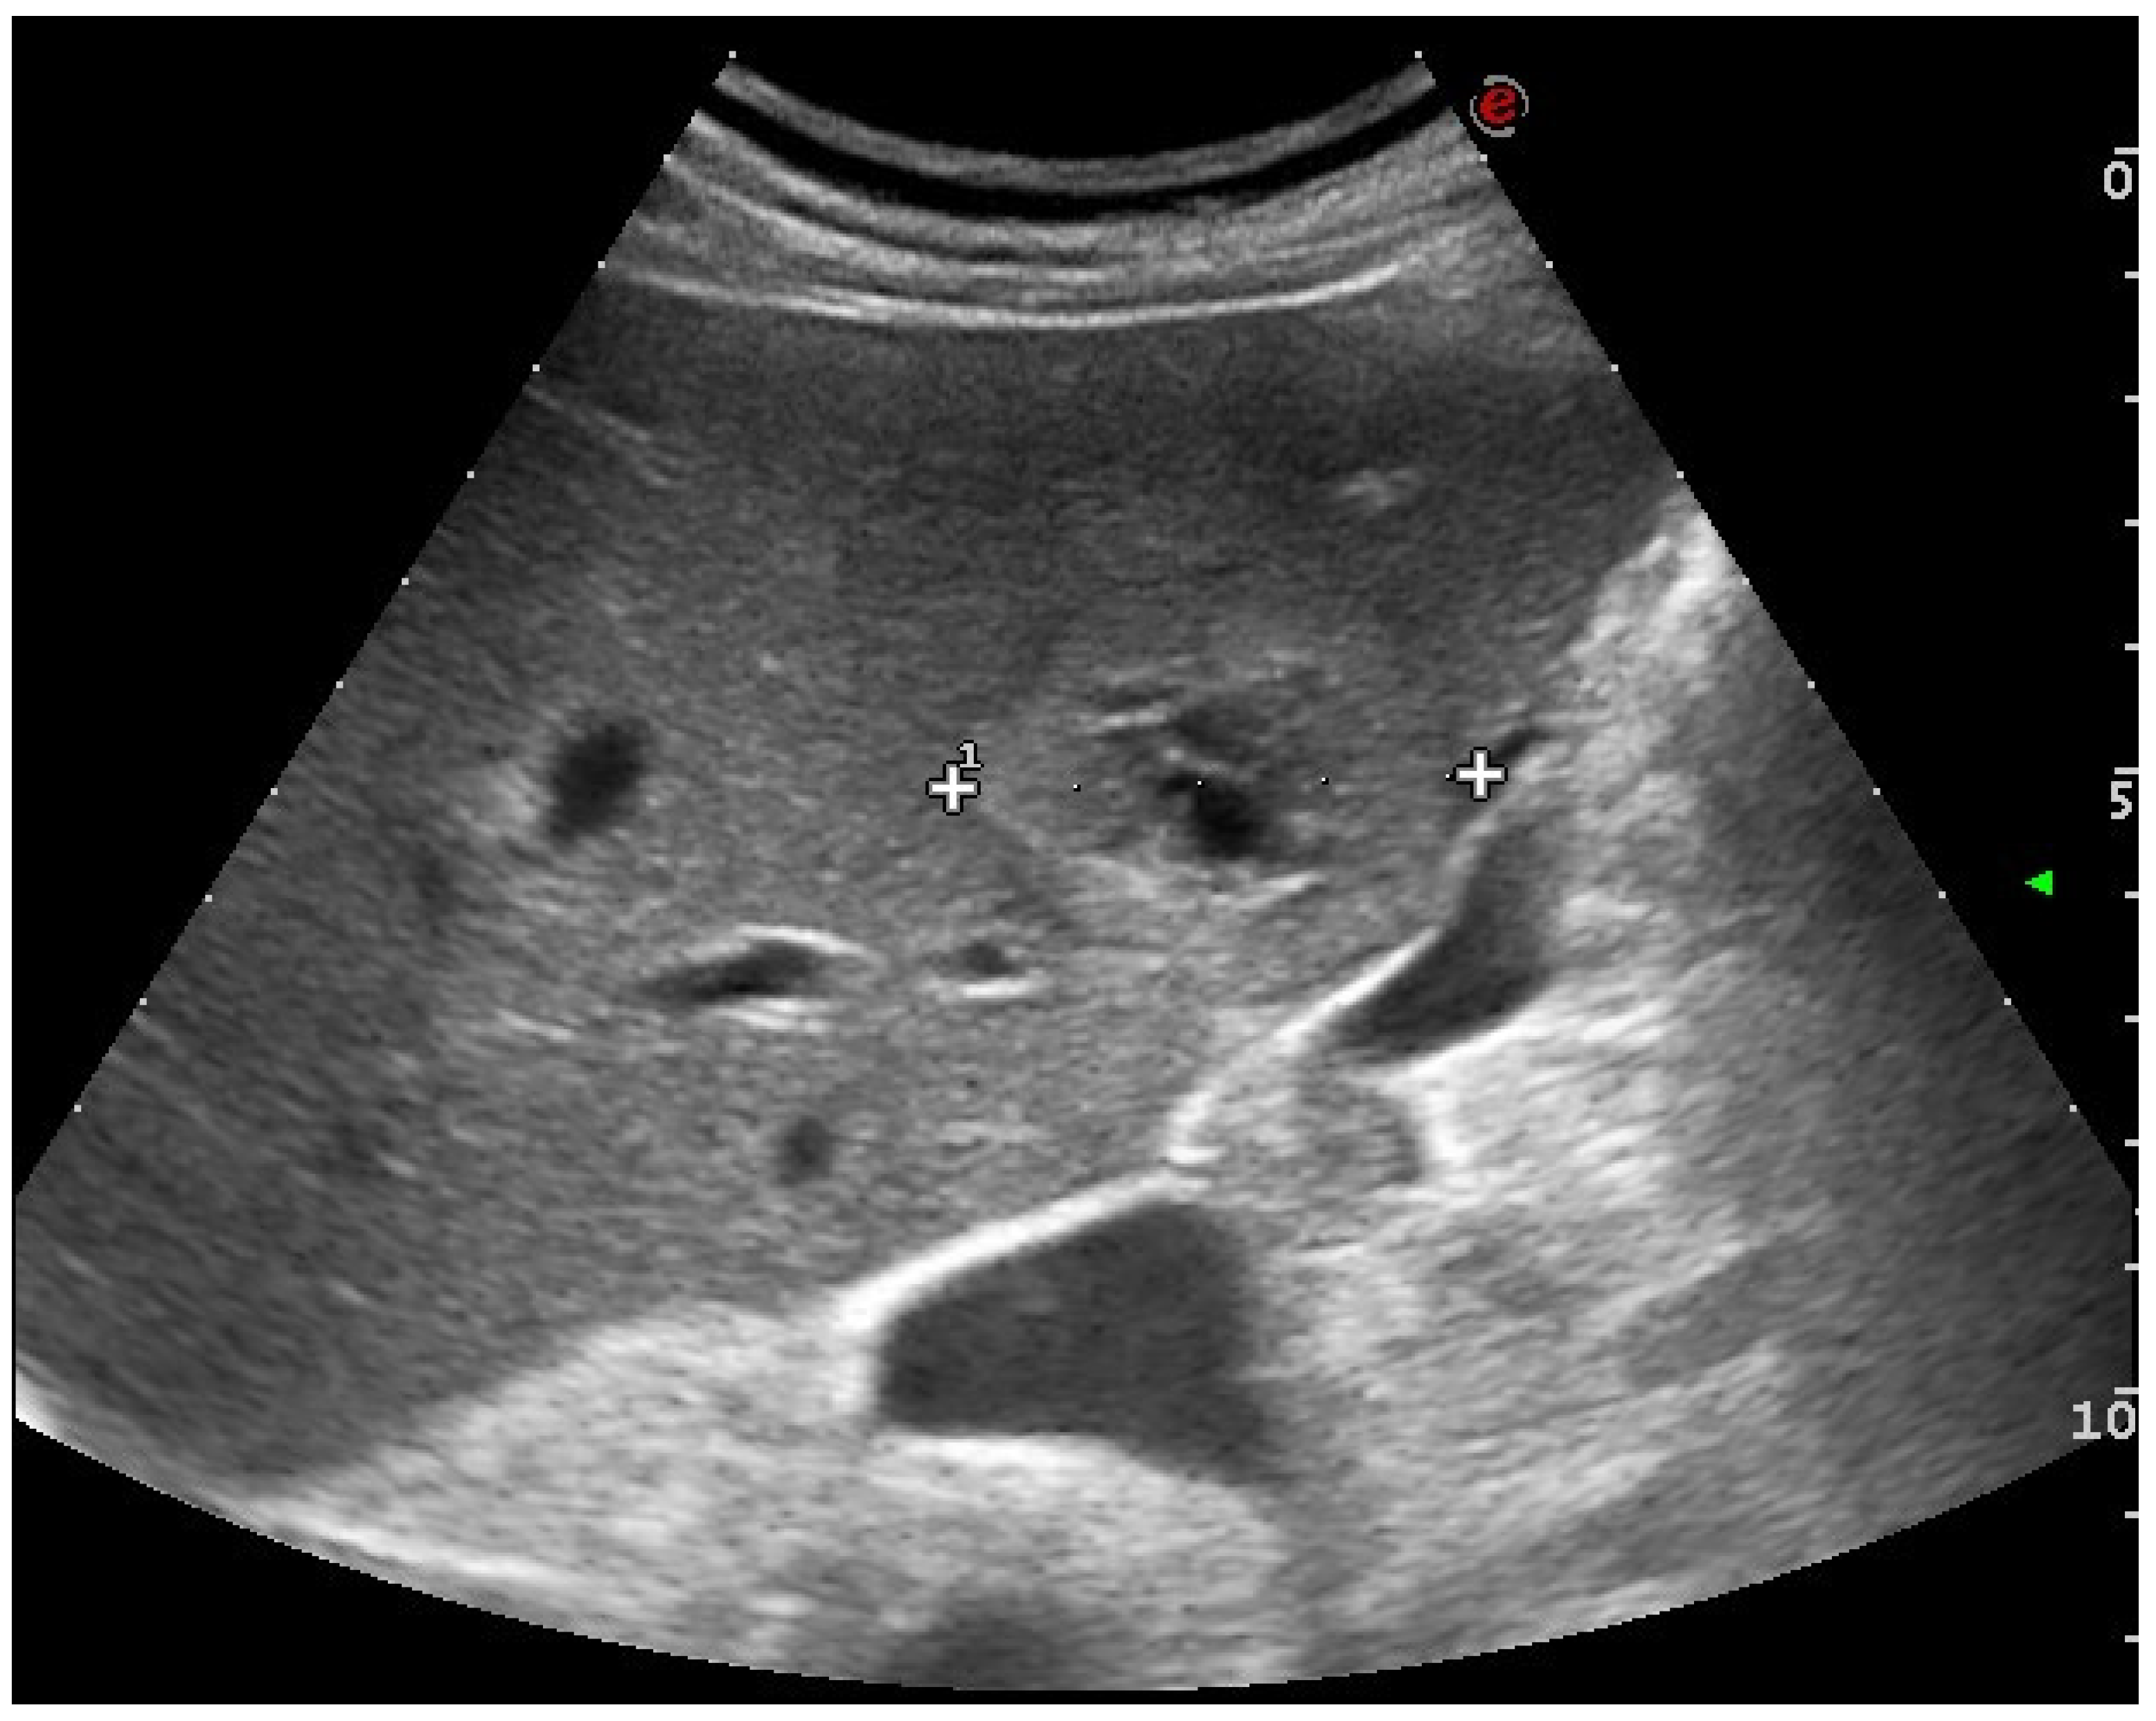

2.1. US and CEUS

- D’Onofrio, M.; Mansueto, G.; Falconi, M.; Procacci, C. Neuroendocrine pancreatic tumor: Value of contrast enhanced ultrasonography. Abdom. Imaging 2004, 29, 246–258. [Google Scholar] [CrossRef] [PubMed]

- Hoeffel, C.; Job, L.; Ladam-Marcus, V.; Vitry, F.; Cadiot, G.; Marcus, C. Detection of hepatic metastases from carcinoid tumor: Prospective evaluation of contrast-enhanced ultrasonography. Dig. Dis. Sci. 2009, 54, 2040–2046. [Google Scholar] [CrossRef] [PubMed]

- Dörffel, Y.; Wermke, W. Neuroendocrine tumors: Characterization with contrast-enhanced ultrasonography. Ultraschall Der Med. Eur. J. Ultrasound 2008, 29, 506–514. [Google Scholar] [CrossRef] [PubMed]

- Massironi, S.; Conte, D.; Sciola, V.; Pirola, L.; Paggi, S.; Fraquelli, M.; Ciafardini, C.; Spampatti, M.P.; Peracchi, M. Contrast-enhanced ultrasonography in evaluating hepatic metastases from neuroendocrine tumours. Dig. Liver Dis. 2010, 42, 635–641. [Google Scholar] [CrossRef] [PubMed]